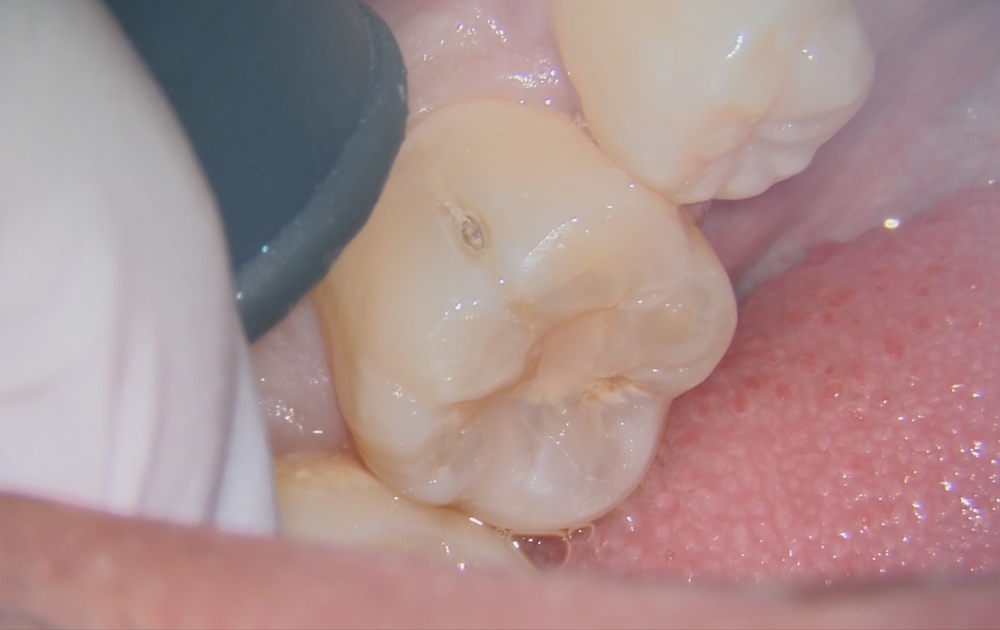

• 1.削る前の最初の状態です。表面にはごく小さな穴が開いているだけですが、この段階では内部の広がりは外から判断できません。

1.削る前の最初の状態です。

表面にはごく小さな穴が開いているだけですが、この段階では内部の広がりは外から判断できません。